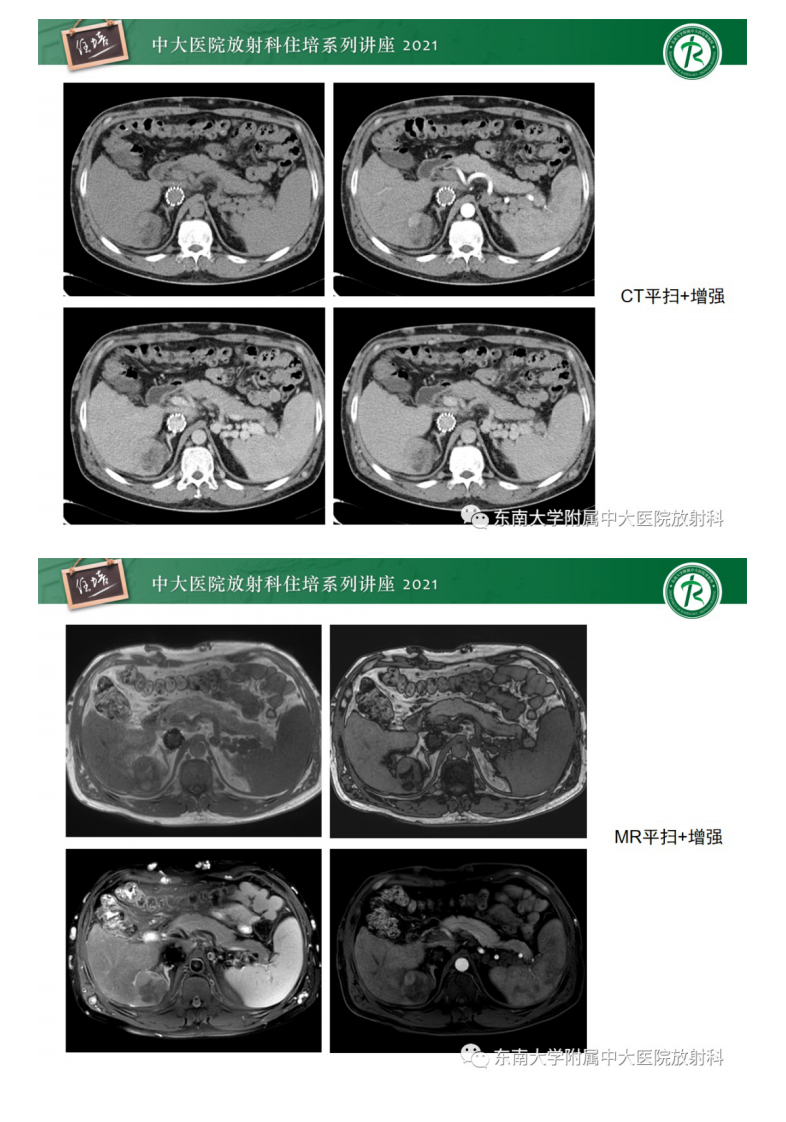

20210418_2【中大放射住培系列讲座】肝脏常见含脂病变.pdf